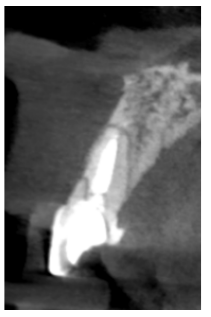

Caso clínico: Se presenta el caso de una paciente mujer de 32 años de edad, que acude por presentar una posible fractura radicular del incisivo central superior izquierdo (ICSI), acompañada de la aparición de un absceso periodontal en la región del fondo de vestíbulo de dicho diente. Tras llevar a cabo la exploración clínica y radiológica, se establece que el pronóstico del ICSI es desfavorable para llevar a cabo un tratamiento conservador del mismo. Tras la valoración de las características clínicas del caso presente, el plan de tratamiento se inclinó por la realización de la exodoncia del ICSI con la colocación simultánea de un IOI postextracción y la carga inmediata con una prótesis provisional del mismo.

Clinical case: We present the case of a 32-year-old female patient who presented with a possible root fracture of the upper left central incisor (ULCI), accompanied by the appearance of a periodontal abscess in the region of the bottom of the vestibule of said tooth. After carrying out the clinical and radiological examination, it is established that the ULCI prognosis is unfavourable for carrying out conservative treatment of the tooth. After assessing the clinical characteristics of the present case, the chosen treatment plan was to extract the ULCI with the simultaneous placement of a post-extraction osseointegrated implant (OII) and immediate loading of a provisional prosthesis on the implant.